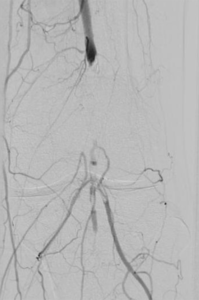

5. Thrombektomie – mechanische Entfernung von Blutgerinnseln

Wenn ein Gefäß durch Blutgerinnsel verschlossen ist, kann man den Verschluss mechanisch wiedereröffnen, indem man die Ablagerungen über spezielle Katheter absaugt. Dazu stehen uns Kathetersysteme, die mit Vakuum arbeiten bzw. zusätzlich die Gerinnsel vor dem Absaugen mit Hilfe von Wasserstrahlen oder Rotation der Katheterspitze zerkleinern, zur Verfügung.